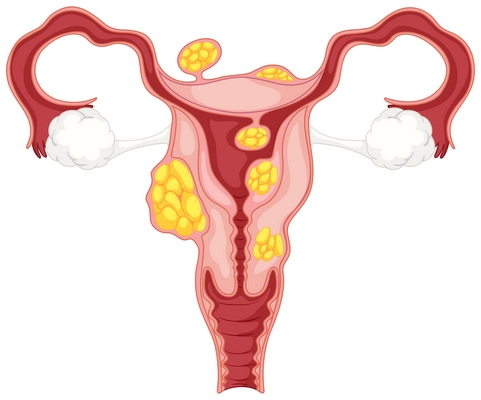

- Myom Tedavisi

- Polikistik Over Sendromu (PKOS)

- Endometriozis ve Çikolata Kisti Tedavisi

- Yumurtalık Kistleri